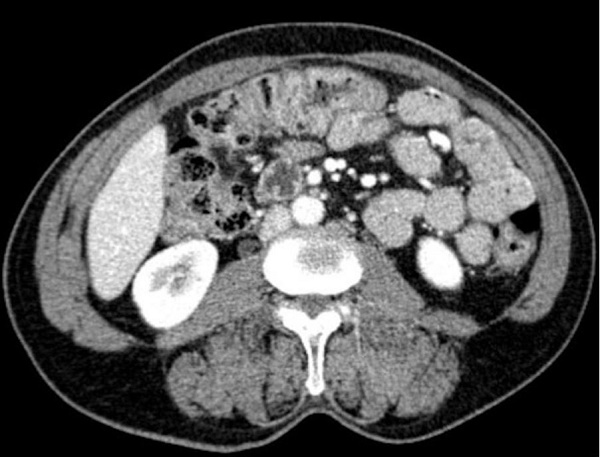

By the end of 10 months on oral amoxicillin, she repeated a CT scan (Figure 3) that revealed the absence of any residual tumor lesion. All the inflammatory process was resolved with the normal anatomical restoration of the involved structures, what permitted the antibiotic withdrawal.